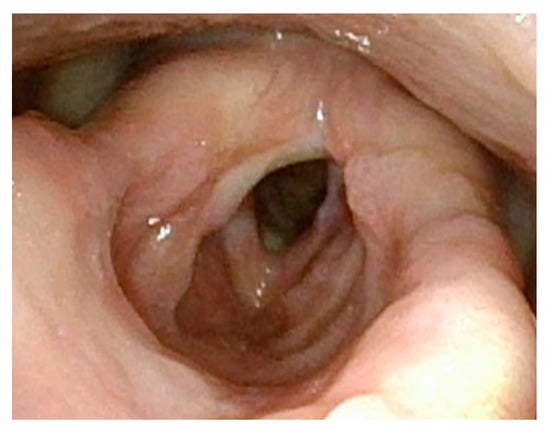

Figure 6.

Significant posterior glottic web with papillomas causing near-complete obstruction of the airway.